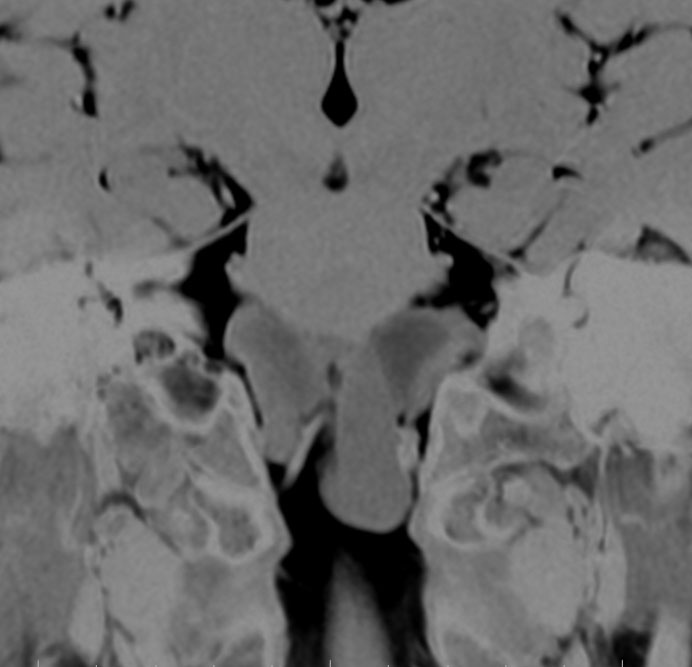

CTでは壁が厚く高密度,MRI T2強調画像では低信号,T1強調画像では高信号です。内部に血液を含んでいるようなのう胞に見えます。のう胞の壁は非常に厚く硬いものが予想されます。閉塞性水頭症になっています。

若い男性ですが,内視鏡手術では摘出できない壁がガチガチのものでした。モンロー孔が広いので経脳梁到達法 transcallsal approachで手術しました。右前頭部から入ろうとしましたが,架橋静脈のために入れず,左前頭葉を除けて,透明中隔の正中に達しました。ところが,左の脳弓が菲薄化して広がり腫瘍の上面にみえましたから,左のモンロー孔からは摘出できませんでした。しかたがないので,右のモンロー孔から腫瘍を摘出しています。腫瘍の周囲には第3脳室脈絡叢が広範囲に癒着していました。のう胞内容は暗褐色の古い血腫でした。のう胞の壁は硬く厚い結合織で肉芽腫のような肉眼所見でした。左右の脳弓にも癒着し,内大脳静脈にも癒着していたので,その部分には皮膜を残しました。

術後のMRIです。幸い,記憶障害などの脳弓症状はでませんでしたが,かなりリスクの高い手術でした。